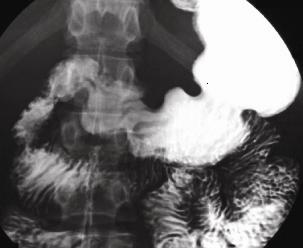

| images TOGD de oesophage

normale |

image TOGD de oesophage (

angle de His ) et estomac normale |

Images normales de estomac , bulbe et

duodenum expose en serie |